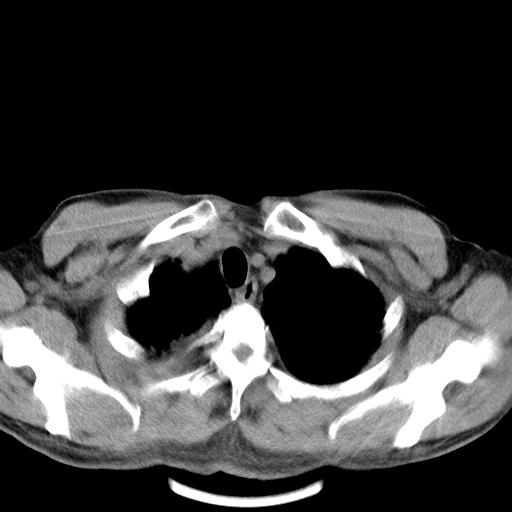

以下是引用zjzjr在2010-3-21 17:39:00的发言:[br]右下中心型肺癌并阻塞性肺炎/不张,纵膈淋巴结肿大,右侧大量胸腔积液,左侧少量胸腔积液

以下是引用zxl51642在2010-3-21 17:06:00的发言:[br]右下中心型肺癌并阻塞性肺炎/不张,纵膈淋巴结肿大,右侧大量胸腔积液,左侧少量胸腔积液,少量腹水。建议纤维支气管镜进一步检查。